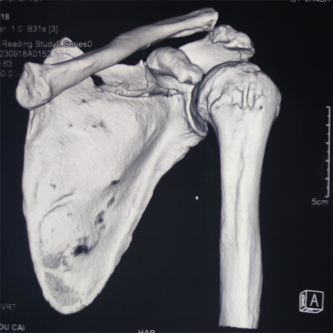

(应用机器人设计钉道)

患者因交通事故致伤导致左肩关节盂骨折及左肩锁关节脱位和右尺桡骨骨折,骨折移位明显,疼痛剧烈,具备手术指征。但患者为75岁高龄,基础疾病多,担心患者无法耐受过大的手术创伤。经术前讨论,创伤外科中心张立峰教授团队决定为患者应用骨科手术机器人辅助经皮内固定治疗肩关节盂骨折的手术方案。术中,通过机器人进行采集数据、并规划手术等人工智能操作,仅用1cm切口即成功完成手术。

“天玑”Ⅱ骨科手术机器人用于辅助医生精确定位植入物或手术器械,可广泛应用于骨科手术,其临床精度可达1mm以内。自2021年91直播 成功引进后,已完成各类骨科手术。本次应用骨科机器人进行肩关节盂骨折手术治疗,进一步拓展了“天玑”II骨科机器人的诊疗范围,完美呈现了“人机结合”,更为创伤急救中心的创新治疗带来新思路。创伤外科中心将继续充分利用骨科机器人的技术优势在新的领域开展临床治疗,提高自治区创伤救治水平,更好地造福患者。